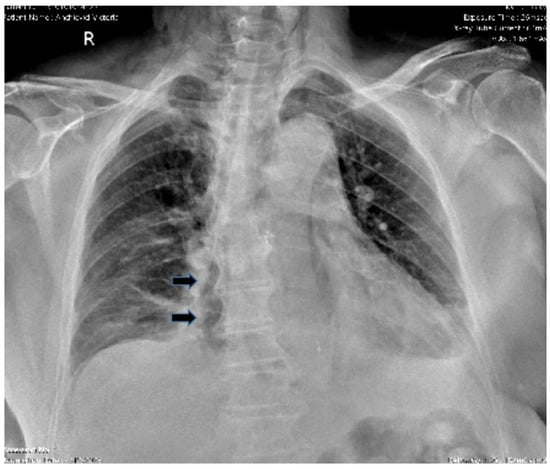

- Pneumomediastinum

- Pneumothorax (especially left-sided)

- Pleural effusion (especially left-sided)

- Localized periaortic gas

- Mediastinal fluid collections

- Thickened esophageal wall

- Gas within thoracic soft tissues, neck, or around major vessels

- Gas in the epidural space

- Pneumoperitoneum

- Gas in the retroperitoneal space

- Oral contrast extravasation from the esophageal lumen [10].

- Air confined to the anterior mediastinum

- Presence of pulmonary emphysema

- Absence of pleural effusion

- Absence of pneumoperitoneum [89].